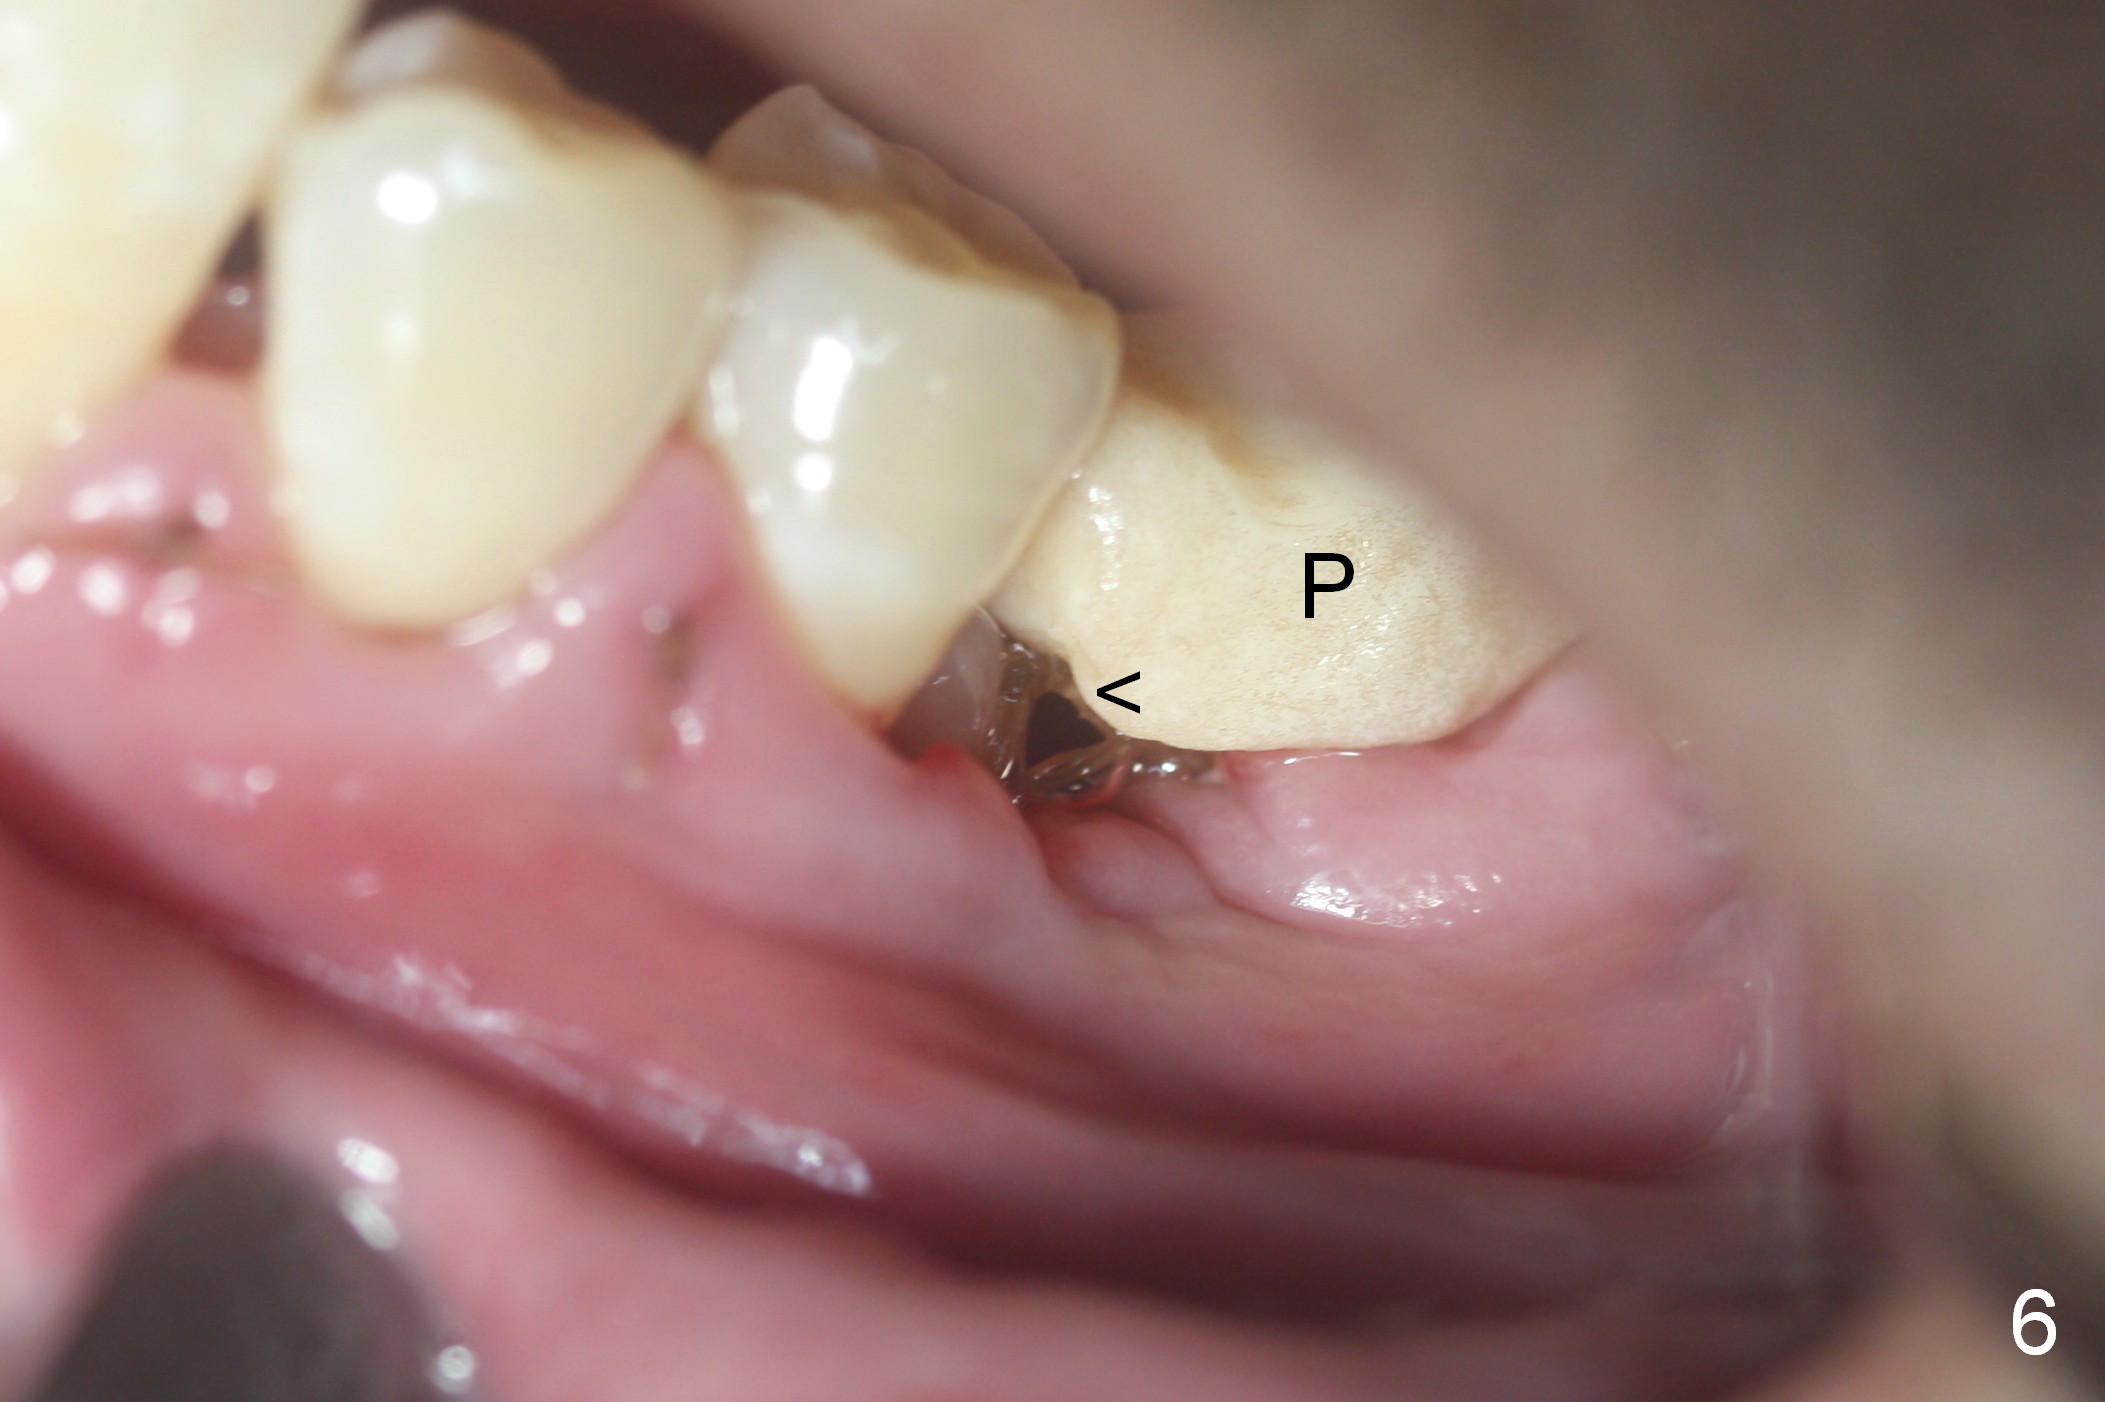

Considering the severe bone loss in the meisal socket, socket preservation is indicated if immediate implant is not feasible. Preop exam shows that the mesiobuccal gingival recession (Fig.1 MB) is not as severe as the mesiolingual one (Fig.2 ML). Because of oozing from the mesial socket, buccal envelop incision is made with flap raising to increase visibility. Probably due to periodontal infection, pain control is difficult. Osteotomy buccal to the Inferior Alveolar Canal proves to be risky. In addition, osteotomy in the mesial socket is more difficult than the distal one (Fig.3). Once the osteotomy depth is determined relative to the superior border of the Inferior Alveolar Canal (4 mm), the osteotomy depth increases by 2 mm. A 5.5x10 mm implant is placed with insertion torque ~ 35 Ncm (Fig.4); a 15 ° angled abutment (5.5 mm in diameter, 4 mm in cuff) is placed mesially. Then the abutment is turned lingually favorable for restoration (Fig.5), the remaining socket is filled with allograft/Osteogen (*) and Collagen Plug.

The patient is doing well postop. The mesial socket appears to have collapsed 7 days postop (Fig.6 <). The mesial portion of the immediate provisional (P) should have been overbuilt to compensate for the socket with lost buccal and lingual plates.